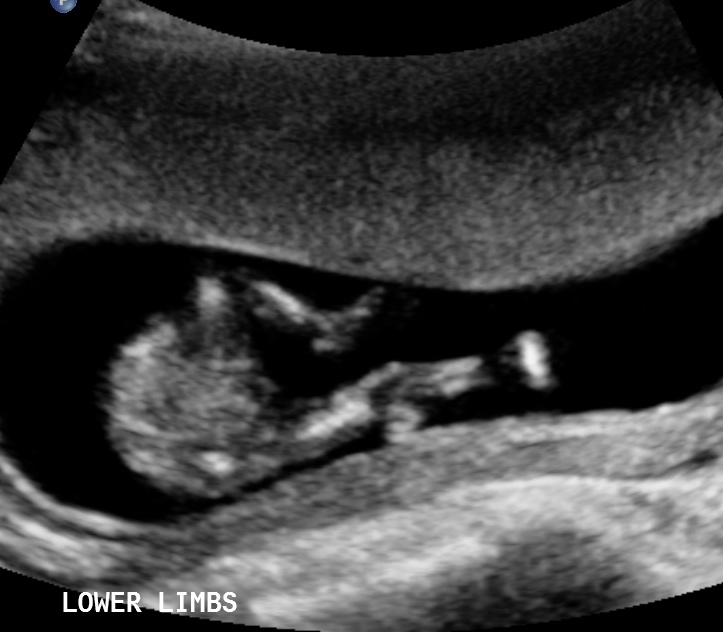

Attachment 37680